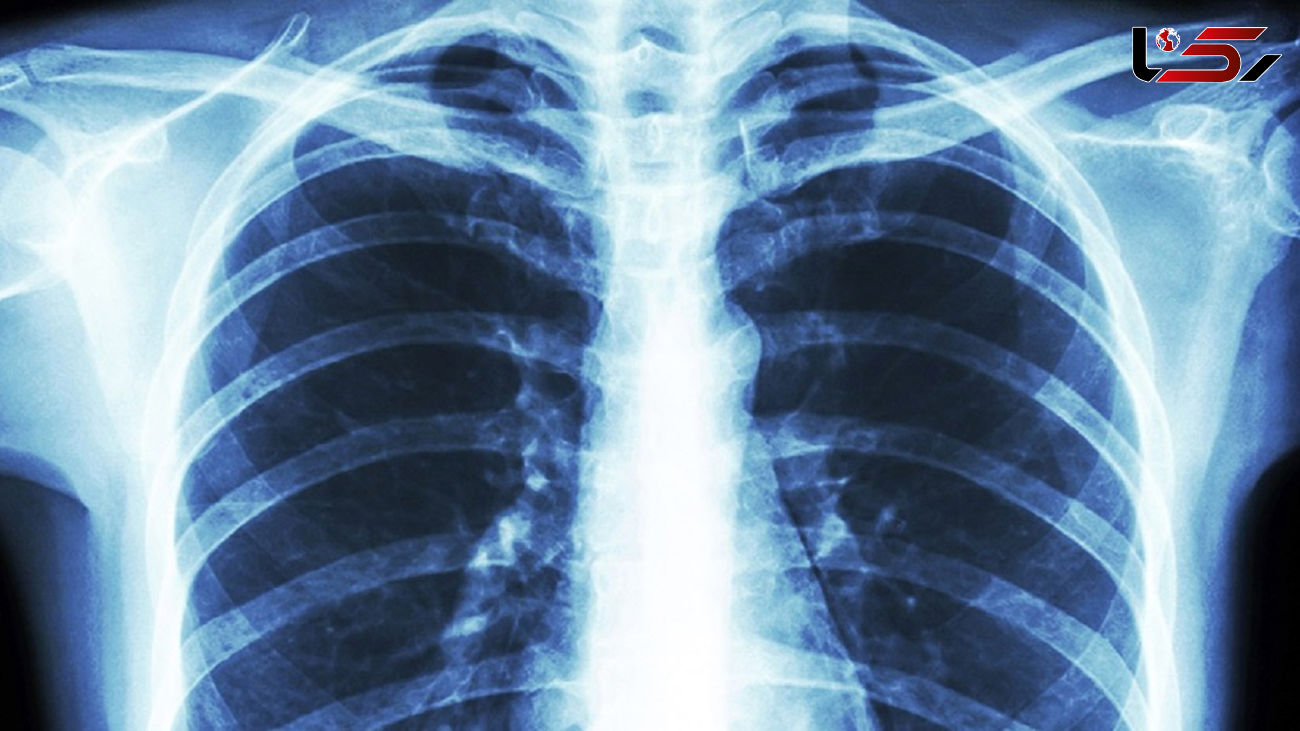

رکنا: یک فوق تخصص بیماری های عفونی از تشدید درگیری ریه پس از بهبودی از کرونا خبر داد.

به گزارش رکنا، دکتر علی معینی با اشاره به درگیری ریه ها در بسیاری موارد ابتلا به کرونا گفت: در مواردی که ابتلا به کرونا در حد متوسط و یا شدید است، درگیری ریه ها به عنوان یکی از عوارض بیماری دیده می شود که می‌تواند بعضا خطرناک باشد.

وی افزود: درگیری ریه ها در بیماری کرونا بطور معمول با علائمی چون سرفه و تنگی نفس خود را نشان می‌دهد و اینطور نیست که ریه ها درگیر شده و فرد بدون علامت باشد.

معینی گفت: البته مواردی داریم که در افرادی که دچار علائم خفیف کرونا شده اند بعد از سه تا چهار روز به یکباره ریه ها درگیری شدید پیدا کرده و حتی منجر به فوت بیمار می‌شود که این امر بسته به سن افراد مبتلا و قدرت سیستم ایمنی بدن آنها و وجود برخی بیماریهای زمینه ای دارد.

این متخصص بیماری های عفونی خاطرنشان کرد: در همین راستا مراجعه سریع به پزشک با وجود علائم خفیف بسیار حائز اهمیت است و بهتر است افراد در صورت داشتن علائم خفیف برای تشخیص کرونا تست PCR بدهند و در صورتی که علائمی مانند سرفه و تنگی نفس دارند توصیه می شود از سی تی اسکن برای تشخیص میزان درگیری ریه ها استفاده کنند.

معینی با اشاره به پایدار بودن عوارض کرونا گفت: در برخی مبتلایان کرونا مواردی داریم که افراد پس از بهبودی کامل همچنان علائمی مانند سرفه و تنگی نفس دارند و باید گفت این سرفه ها و این تنگی نفس دیگر علائم کرونا نیستند، بلکه عوارض به جا مانده از این بیماری می‌باشند.

وی افزود: این عوارض که شامل درگیری ریه، قلب، مغز و ... می‌تواند باشد، بعد از بهبودی کامل هم امکان پیشروی و بدتر شدند دارند و این امکان هست که افراد پس از بهبودی از کرونا به سمت نارسایی تنفسی بروند، بنابراین درمان این عوارض باید تحت نظر پزشک معالج دنبال شود.

معینی گفت: به افرادی که بیماری کرونای آنها بهبود یافته، اما همچنان از سرفه و تنگی نفس رنج می برند توصیه می شود حتما به پزشک مراجعه کرده و روند پیشروی عوارض را رصد کنند تا دچار عارضه جدی نشوند./ایسنا  آخرین قیمت های بازار ایران را اینجا کلیک کنید.